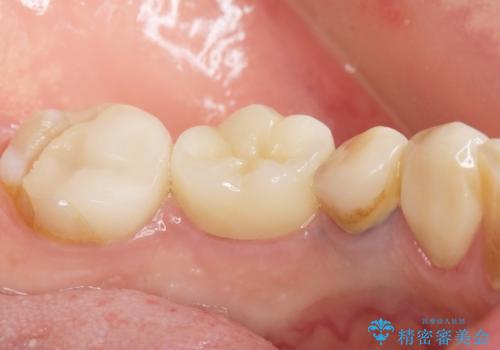

- 奥歯の被せ物をセラミックにしたいとご希望され、来院された患者様です。

左下の奥歯(左下6)の劣化した白い被せ物と金属の土台を除去し、セラミッククラウンによる補綴治療を行いました。

セラミッククラウンの天然歯のような自然な仕上がりと咬み心地に喜んで頂けました。

クラウンの種類:オールセラミッククラウン スタンダード